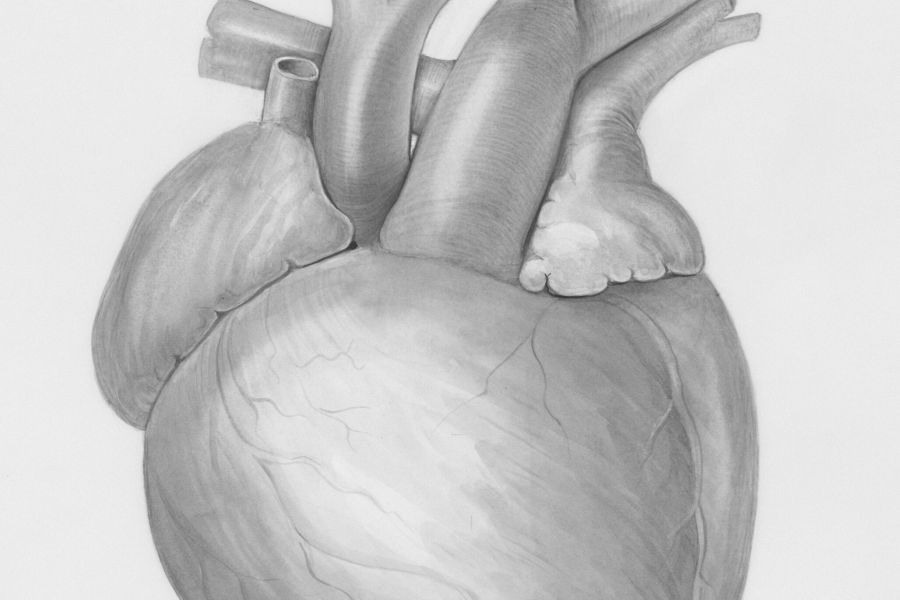

Informatiemarkt over hartfalen in Franciscus

Tijdens de Nationale Hartfalenweek vraagt Franciscus aandacht voor hartfalen, een aandoening die ongeveer een half miljoen Nederlanders treft. Om patiënten en geïnteresseerden te informeren en ondersteunen, organiseert Franciscus op dinsdag 21 april een gratis informatiemarkt in de Centrale Hal van Franciscus Gasthuis in Rotterdam. Bij hartfalen pompt het hart minder goed bloed rond, wat grote […]

Ook actieve sporters kunnen last hebben hart- en vaatziekten

Nieuwe adviezen bieden sporters van middelbare en hogere leeftijd meer ondersteuning Lang werd gedacht dat sporten alleen maar voordelen heeft voor de gezondheid. Recent onderzoek laat zien dat een zeer intensieve sportieve leefstijl in sommige gevallen ook risico’s met zich mee kan brengen. Daarom hebben Europese en Amerikaanse cardiologieverenigingen hun kennis gebundeld, zodat artsen hart- […]